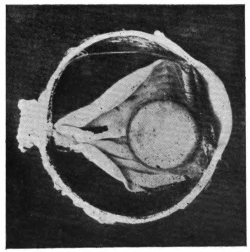

NUCLEUS OF CATARACT FREELY MOVABLE BETWEEN THE AQUEOUS AND VITREOUS CHAMBERS

12.

LENS IMPACTED IN ANGLE OF ANTERIOR CHAMBER

13.

CAPSULE OF MORGAGNIAN CATARACT IMPACTED IN ANGLE OF ANTERIOR CHAMBER

14.

LENS FLOATING FREE IN VITREOUS CHAMBER

15.

LENS LIGHTLY IMPRISONED IN EXUDATE INTO VITREOUS CAVITY